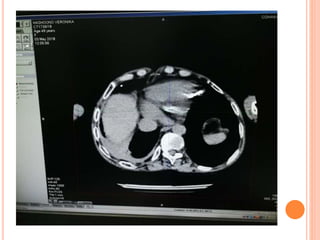

CT scans

Bony Window,

Sagittal view

coronal view

Mediastinal Window

Lung Window